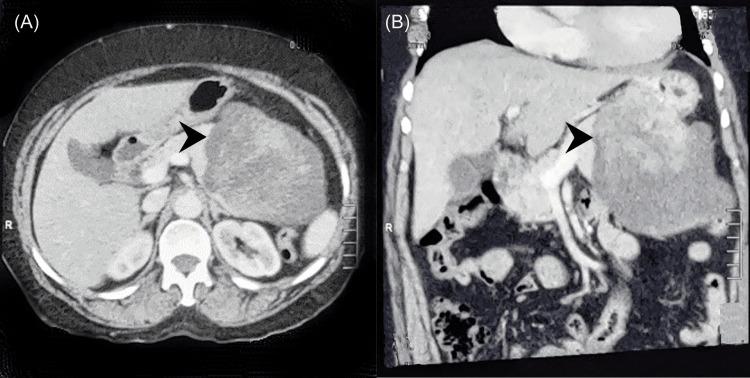

During this period, eight cases were diagnosed with SPN. All patients were female with a median age of 25.75 years (range 14-55 years). All cases presented with pain in the abdomen, and four patients had a mass per abdomen. In all the cases, contrast-enhanced computed tomography (CECT) abdomen was done for the diagnosis and had preoperative suspicion of the pseudopapillary tumor. In four cases, the tumor was located in the head region, while in four cases, the tumor was in the body and tail of the pancreas. The median size of the tumor was 12 cm (range 3.5-15 cm). Three cases underwent Whipple's procedure and one patient was unresectable. Two out of four patients with body and tail tumors underwent distal pancreatectomy with splenectomy, one underwent spleen-preserving distal pancreatectomy, and one patient underwent central pancreatectomy.

在此期间,8例被诊断为SPN。所有患者均为女性,中位年龄25.75岁(范围14 - 55岁)。所有病例均表现为腹痛,4例患者腹部可触及肿块。所有病例均行腹部增强计算机断层扫描(CECT)以进行诊断,术前均怀疑为假乳头状瘤。4例肿瘤位于胰头区域,4例肿瘤位于胰腺体尾部。肿瘤中位大小为12 cm(范围3.5 - 15 cm)。3例行Whipple手术,1例患者无法切除。4例体尾部肿瘤患者中,2例行胰体尾切除术加脾切除术,1例行保留脾脏的胰体尾切除术,1例行胰中段切除术。